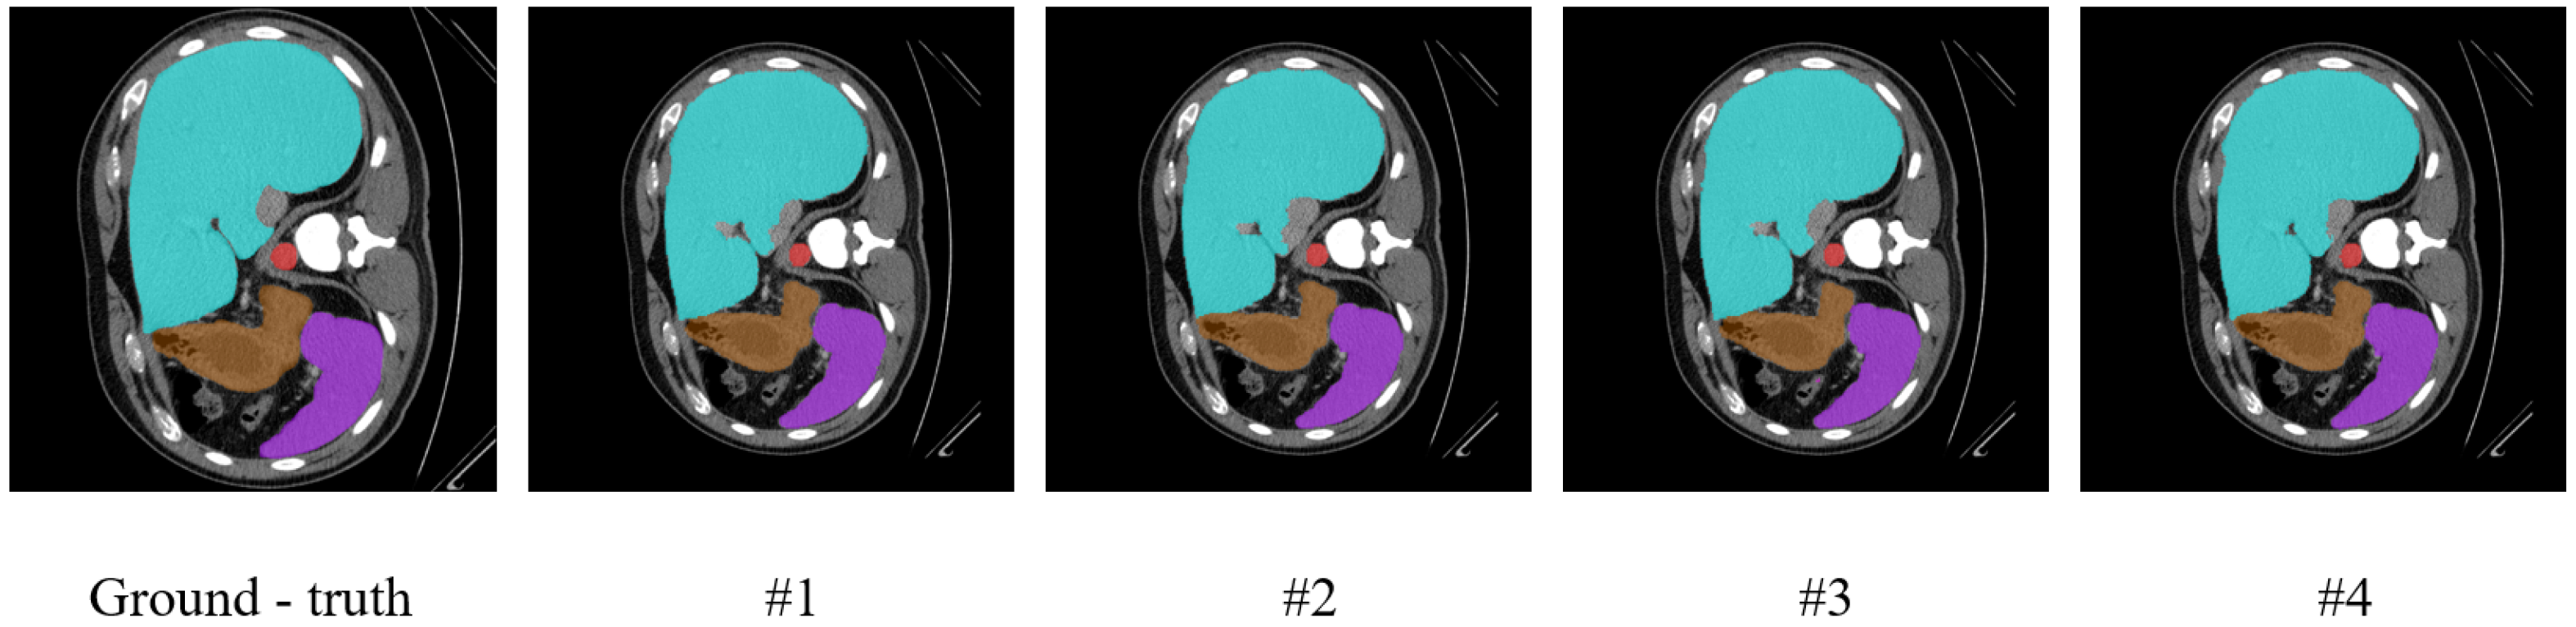

To further visually verify the effectiveness of the key components in our model, we conducted visualization experiments, the results of which are presented in Figure 8 and Figure 9. The figures show visualization maps of the segmentation results on the Synapse and ISIC-2018 datasets when different key components were removed (corresponding to settings #1, #2, and #3 in Table 4), as well as for the complete MRCA-UNet model (#4). By comparing these visual results, the contribution of each module to the final segmentation effect can be more clearly understood.

Figure 8. Visualization results of the ablation study on the Synapse dataset.